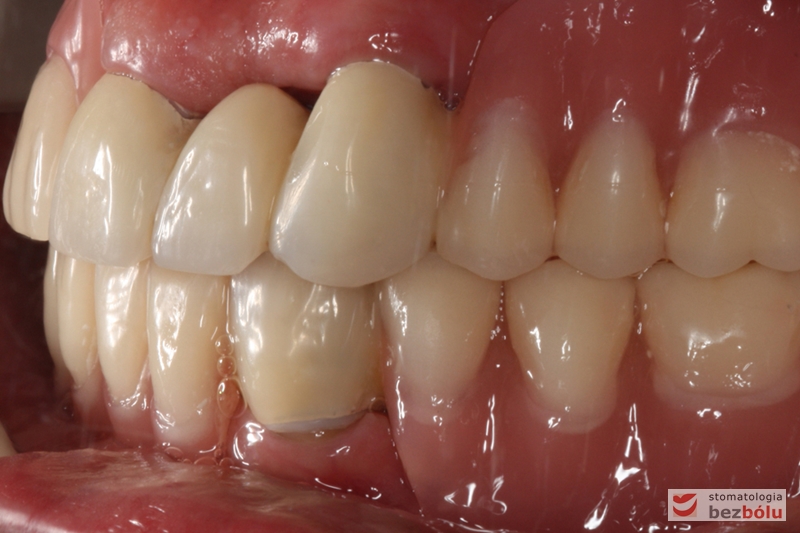

Ostateczny efekt terapeutyczny - zadowolona i uśmiechnięta pacjentka

Ostateczny efekt terapeutyczny – zadowolona i uśmiechnięta pacjentka